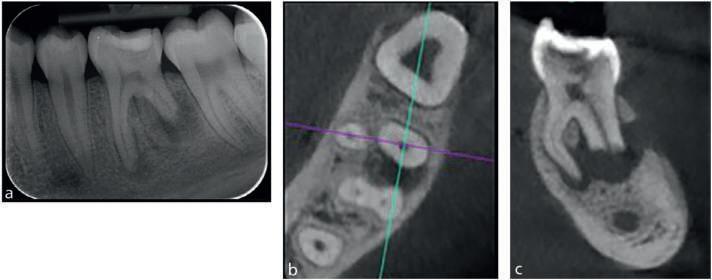

Among the more challenging treatments are those related to bringing impacted teeth into the arch. Often these teeth are engaged with other teeth, so the orthodontist must be aware of the vector of force needed to move the tooth without causing resorption of the roots of adjacent teeth or other problems. The orthodontist must inform the patient and parents about the risks and alternative approaches to recovering impacted teeth before treatment is begun. In addition, the orthodontist should obtain cone-beam computed tomograms of the area to aid diagnosis and treatment planning. In some cases, the teeth don’t move or become ankylosed during movement, with reciprocal movement. In these cases the orthodontist must reevaluate the situation before proceeding further.